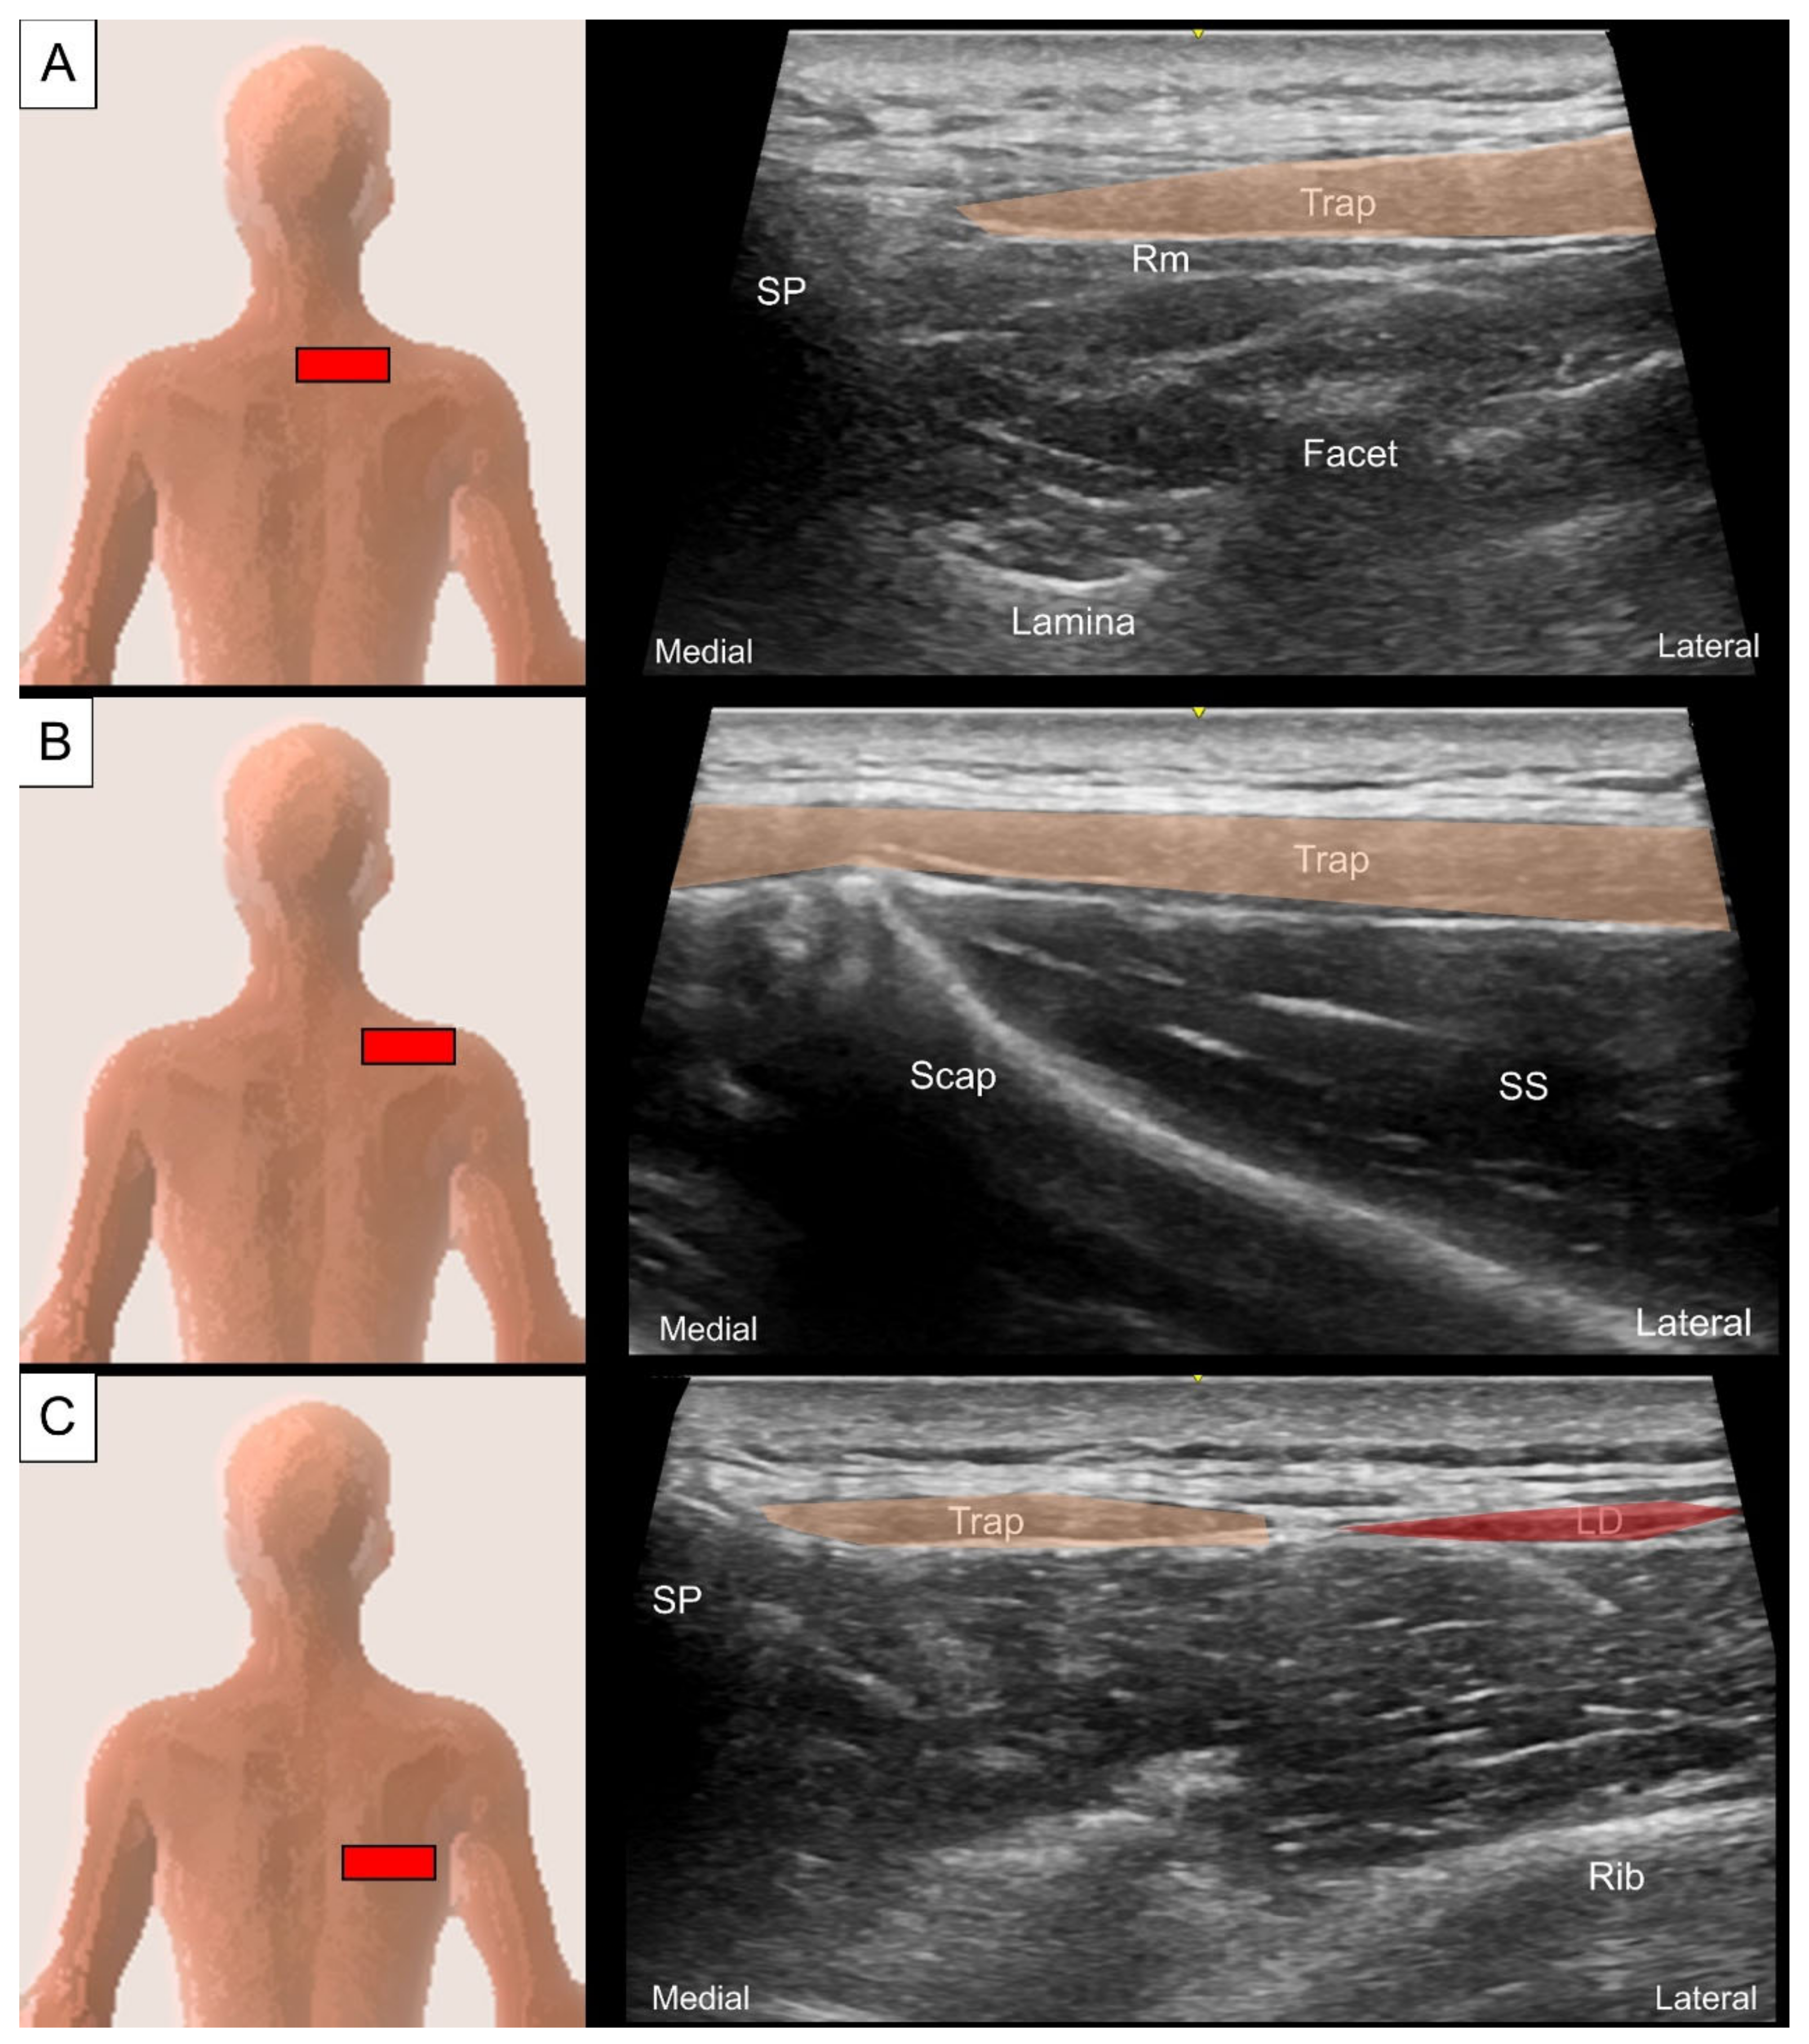

2.1. Trapezius and Latissimus dorsi

2.1.2. Sonographic Scanning

2.1.3. Clinical Relevance